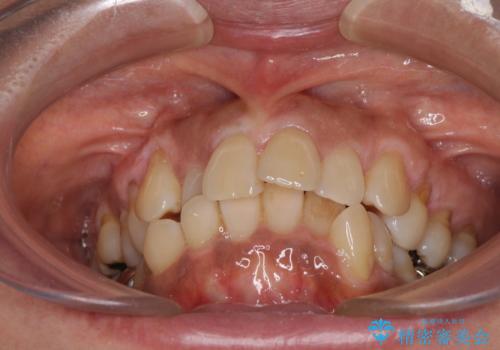

- 八重歯やクロスバイトを気にして来院された患者様です。

口元の突出感はありませんでしたが、デコボコが強く、非抜歯矯正とすると出っ歯仕上がりとなる可能性があったため、上下左右の第一小臼歯4本を抜歯し、ワイヤー装置にて矯正治療を行うこととしました。